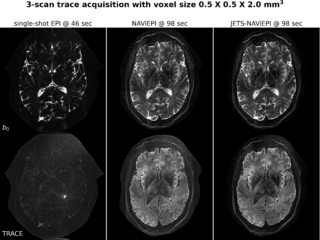

We are very happy to announce that our most recent manuscript (https://doi.org/10.1162/imag_a_00085) has just been published in early view in Imaging Neuroscience. We introduced a novel diffusion MRI acquisition and reconstruction approach for ultra-high field (7T) imaging. Our method consists of a navigator-based interleaved echo-planar imaging (NAViEPI) sequence and a joint-k-q-slice reconstruction for shift-encoded sampling (JETS). This enforces consistent effective echo spacing between imaging and navigator echoes, enabling (1) minimal distortion mismatch between echoes, (2) reliable shot-to-shot phase variation estimation, and (3) flexible number of shots for sub-millimeter resolution. Our approach achieves 0.5 x 0.5 x 2.0 mm3 diffusion MRI with whole brain coverage in a scan time of only 98 seconds. Our work is in collaboration with the Ultra-High Field Pre-Development Team at Siemens Healthineers and is the first publication out of our Research Unit grant that was recently funded by the German Research Foundation (DFG, Research Unit 5534 – MR biosignature at UHF).